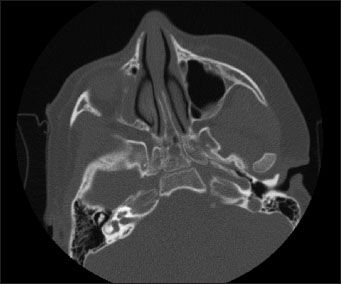

Figure 2 – A head CT scan revealed complete opacification of the right maxillary sinus, indicative of sinusitis. The left maxillary and sphenoidal sinuses appeared normal. The frontal sinus is typically not well developed in this age-group.

In a child with THI, the initiation of physiologic IgG production is delayed. The precise cause of the delay is not known.1 However, it is theorized that a defect in the number and function of T helper cells may hinder the differentiation of B cells into antibody producers (although there is no intrinsic defect in the B cells themselves).1,4 As acquired IgG is metabolized, IgG levels do not recover at a normal rate. A prolonged immunodeficiency results. The deficiency is manifested in recurrent infection-most commonly otitis media, chronic cough, and bronchitis.1 Shapiro and colleagues5 have also correlated IgG deficiency with chronic sinusitis. In this patient, THI has manifested most frequently as sinusitis over the past 3 years (Figure 2).